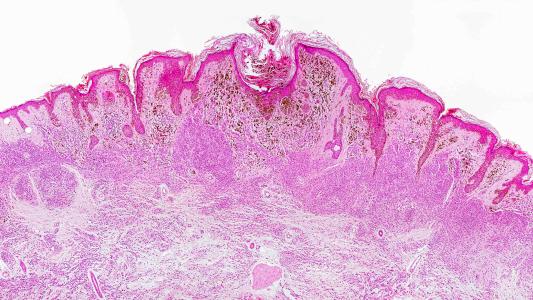

Urine test could replace malignant melanoma biopsies

Doctors can look to the levels of certain fluorescent molecules in the urine of malignant melanoma patients to track the progression of their skin cancer.